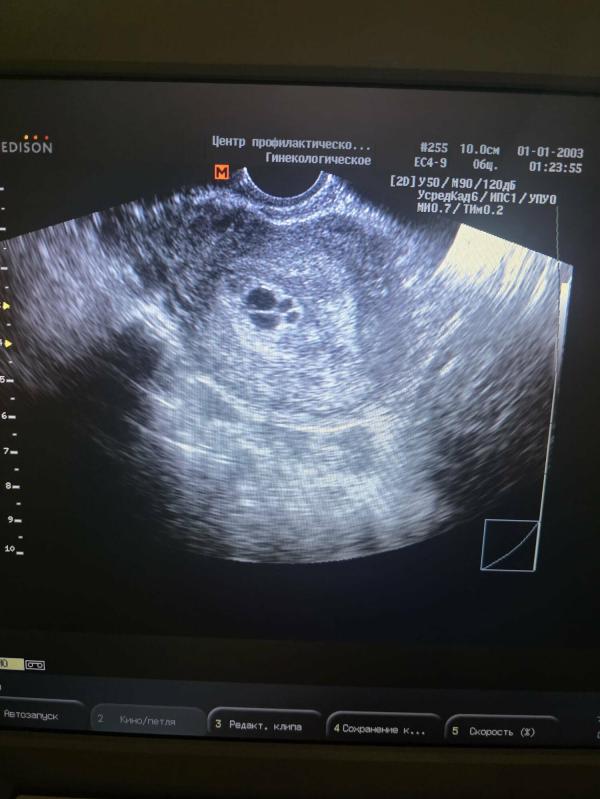

Пузырный занос: какие симптомы, уровень ХГЧ и лечение?

У кого был пузырный занос? Какие симптомы были? Как вел себя хгч,долго личились?

Ничего особенного, увидели картину на узи, потом почистили